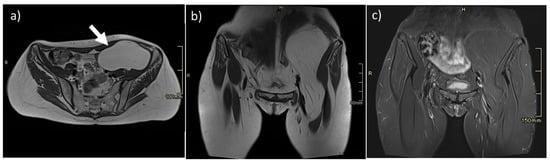

- Desmoplastic Small Round Cell Tumor (DSRCT): rare, highly aggressive sarcoma of adolescents, which primarily involves the serosal surfaces of the abdominal cavity infiltrating the abdominal wall [30,31,32]. Classic findings include bulky multiple, hypoattenuating, soft-tissue masses, with omental, serosal, and rectovesical involvement [31,32] and typical punctate or amorphous calcifications [32]. Modest heterogeneous enhancement is seen on arterial phase, without prolonged enhancement or portal washout [31,32] (Figure 10). On MR, DSRCTs are heterogeneously iso- to-hypointense on T1-w images, with hyperintense foci due to intratumoral hemorrhage [32].